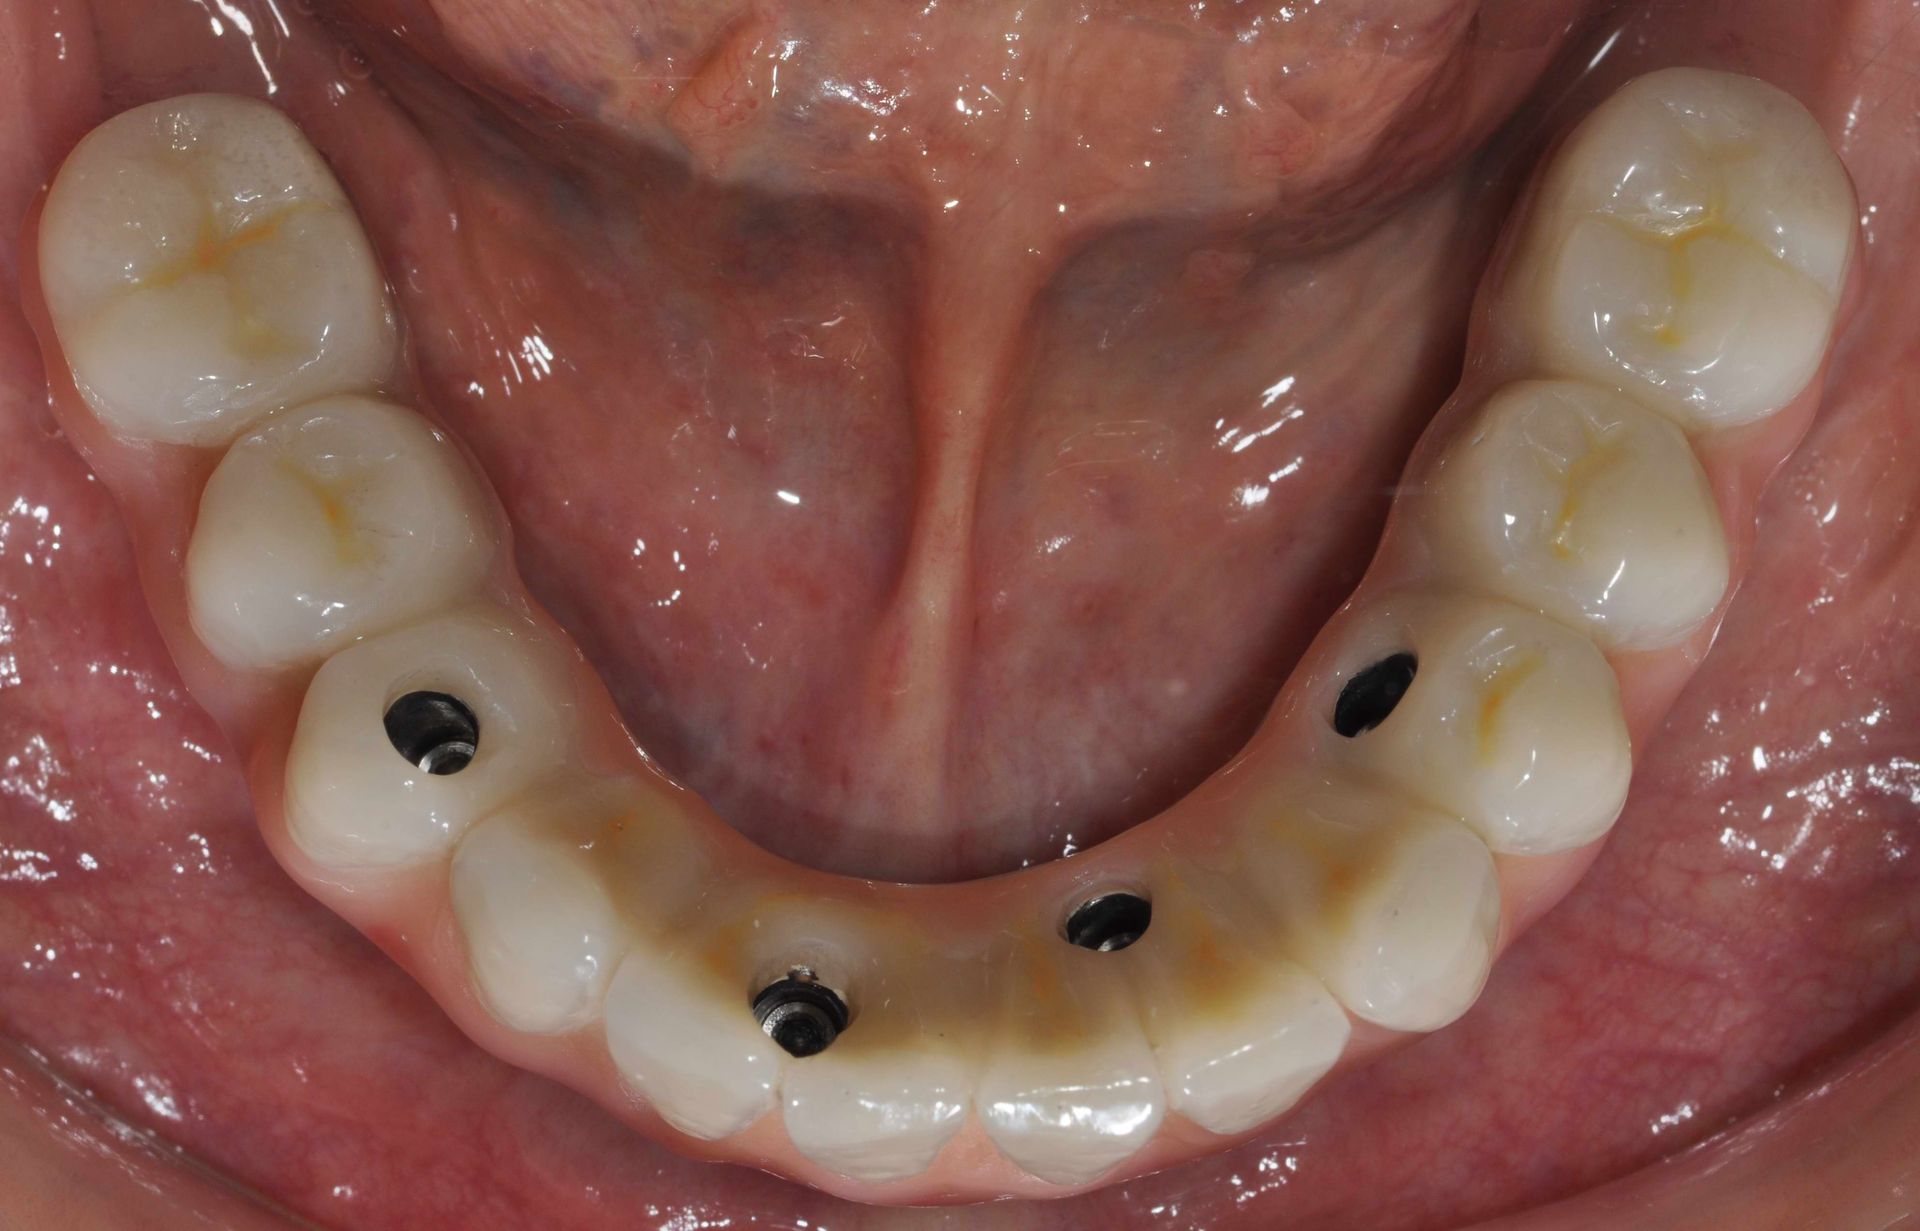

Implantologia

L'implantologia è una branca dell'odontoiatria che si occupa della sostituzione dei denti mancanti attraverso l'inserimento di impianti dentali. Questi impianti, realizzati in titanio biocompatibile, fungono da radici artificiali su cui vengono fissate protesi dentarie come corone, ponti o dentiere. L'implantologia offre una soluzione stabile e duratura per ripristinare la funzionalità masticatoria e l'estetica del sorriso, migliorando significativamente la qualità della vita dei pazienti.